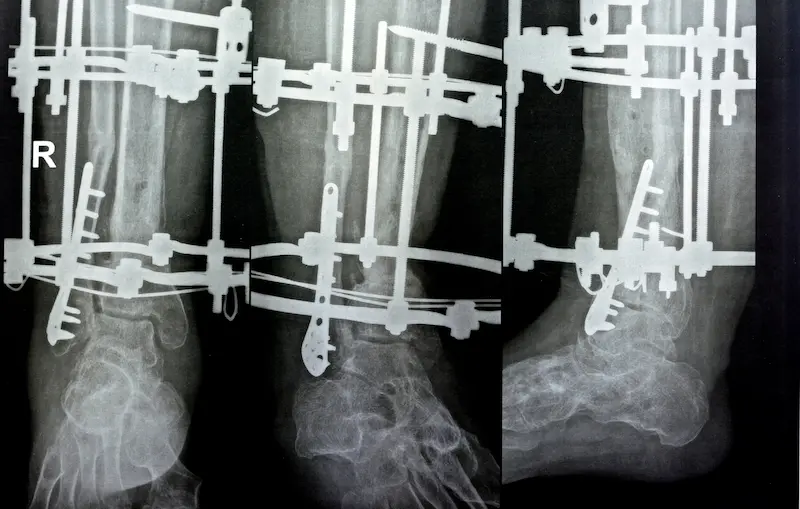

Ключевой вывод: Метод LON (Lengthening Over Nail) — это комбинированный метод удлинения ног, который сочетает использование внутреннего интрамедуллярного штифта и компактного внешнего фиксатора. Это самый популярный и сбалансированный вариант для операции по увеличению роста в Турции, предлагающий надежность по разумной цене.

Принцип работы метода LON заключается в следующем: во время операции в костномозговой канал устанавливается телескопический штифт, а снаружи на ногу монтируется аппарат внешней фиксации. Именно внешний аппарат отвечает за процесс удлинения (дистракции). Главное преимущество в том, что после завершения этапа удлинения (обычно через 2-3 месяца) внешний фиксатор снимается во время простой амбулаторной процедуры. Внутренний штифт остается в кости, выполняя роль прочного каркаса и значительно ускоряя процесс консолидации (затвердевания) новой кости. Это позволяет пациенту гораздо раньше вернуться к ходьбе без костылей.

- Установка конструкции: Далее хирург устанавливает систему для удлинения. Если выбран метод LON, в костномозговой канал вводится интрамедуллярный штифт, а снаружи монтируется внешний фиксатор. Если выбор пал на PRECICE 2, устанавливается только внутренний магнитный штифт.